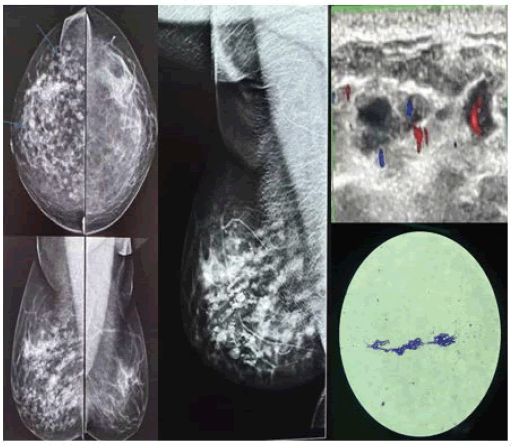

1. Case 1: FCC: a 48-year-old woman came for evaluation of pain (Figure 6).

Figure 6. Digital Mammography (DM): Breast composition-Heterogeneously dense breasts-Category C (Cat. C). An isodense lesion with a hypodense rim whose margins are obscured by adjacent fibroglandular tissue was noted in the upper outer quadrant of the right breast. USG: A well-defined clear cystic lesion with posterior acoustic enhancement. Few small fibrocystic changes are also seen in both breasts. BI-RADS 3. USG guided aspiration: FCC

2. Case 2: Solitary Fibroadenoma: 45-year-old female came with a lump in the right breast (Figure 7).

Figure 7. DM: breast composition-scattered fibroglandular tissue (Category B). A Well circumscribed dense oval solitary mass lesion in the upper outer quadrant of Rt breast. USG: Well defined, large oval isoechoic solid lesion wider than tall with thick echogenic pseudocapsule seen in outer quadrant at 9 o’clock position on USG s/o Fibroadenoma-BI-RADS3

3. Case 3: Giant fibroadenoma: 36-year-old female came with a lump in the right breast (Figure 8).

Figure 8. Digital Mammography (DM): Breast composition-Dense breast (cat D). Showing Large (5.5 cm × 3.4 cm in size) well-circumscribed, round iso to a hyperdense mass lesion in the lower outer quadrant in the mid and posterior portion of Right breast. USG: well-defined hypoechoic lesion with more peripheral vascularity on colour Doppler-BI-RADS 3. After reassessment, Upgraded to BI-RADS 4a and proceeded for biopsy. Histopathology revealed Giant Fibroadenoma

4. Case 4: Central solitary duct papilloma: 68-year-old female came with left nipple discharge (Figure 9).